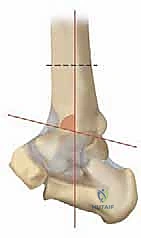

كيف يحدث الخلل الميكانيكي؟

في حالة التشوه التقوسي (Varus Deformity)، يحدث ميلان في المحور الميكانيكي للساق. تخيل أنك تقود سيارة وإطاراتها غير متوازنة (Misaligned). سيؤدي ذلك إلى تآكل جانب واحد من الإطار بسرعة أكبر بكثير من الجانب الآخر. هذا بالضبط ما يحدث في الكاحل التقوسي؛ حيث ينتقل محور تحمل الوزن (Weight-bearing axis) بشكل غير طبيعي نحو الداخل (الجانب الإنسي). هذا التركيز المفرط للإجهاد يفوق قدرة الغضروف على التحمل، مما يؤدي إلى تشققه، تآكله، وفي النهاية تلامس العظم بالعظم، وهو ما يسبب الألم المبرح والالتهاب.

فهم خشونة مفصل الكاحل من النوع التقوسي (Varus Ankle Osteoarthritis)

خشونة مفصل الكاحل من النوع التقوسي هي حالة مرضية تدريجية (Progressive) لا تحدث بين عشية وضحاها. إنها تتميز بتشوه تقوسي مع فتح أمامي للسطح المفصلي في الطرف البعيد من عظم الساق. وغالباً ما تظهر هذه الحالة بشكل ثنائي (في كلا الكاحلين)، وتكون أكثر شيوعاً لدى النساء في منتصف العمر وكبار السن، وكذلك لدى الرياضيين السابقين أو الأشخاص الذين تعرضوا لإصابات قديمة.